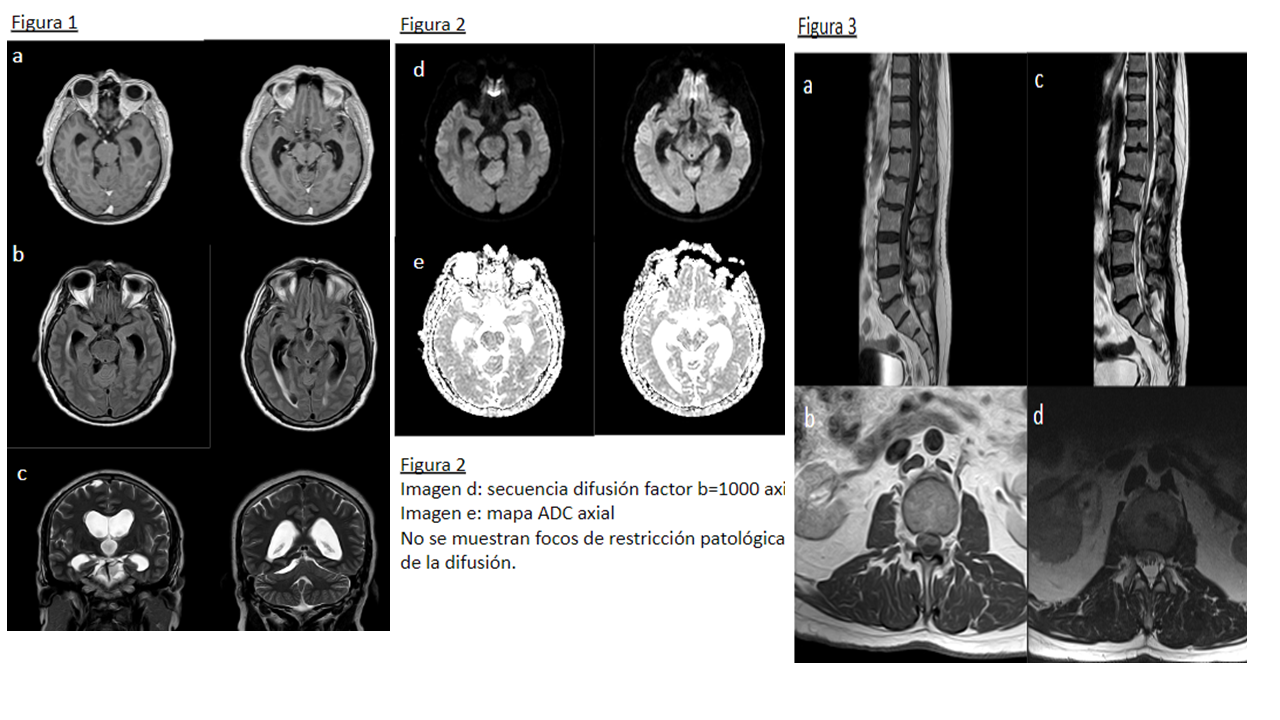

Figura 1 Imagen a: secuencia T1 con contraste axial Imagen b: secuencia FLAIR axial

Imagen c: secuencia T2 coronal Leve ampliación de cisternas de la base craneal, con algún septo, especialmente en la cisterna perimesencefálica y ambiens en el lado derecho con leve distorsión de estructuras encefálicas próximas. No existe realce leptomeníngeo tras la administración de gadolinio. En el T2 coronal se aprecia hidrocefalia supratentorial con edema transependimario y borramiento generalizado de los surcos de la convexidad hemisférica.

Figura 2 Imagen d: secuencia difusión factor b=1000 axial Imagen e: mapa ADC axial No se demuestran focos de restricción patológica de la difusión.

Figura 3 Imagen a: secuencia T1 con contraste sagital Imagen b: secuencia T1 con contraste axial Imagen c: secuencia T2 sagital Imagen d: secuencia T2 axial Las raíces de la cola de caballo se encuentran engrosadas y agrupadas en el centro del saco tecal, con distorsión de su contorno y nodularidad de la superficie, que muestra realce tras la administración de gadolinio.